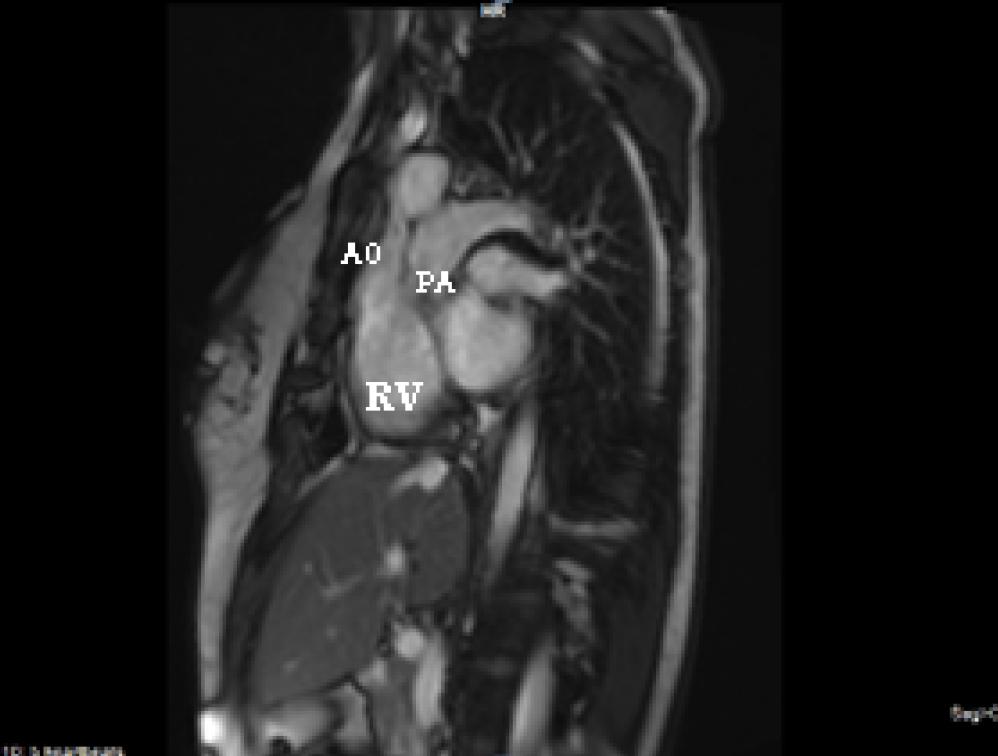

Figure 4